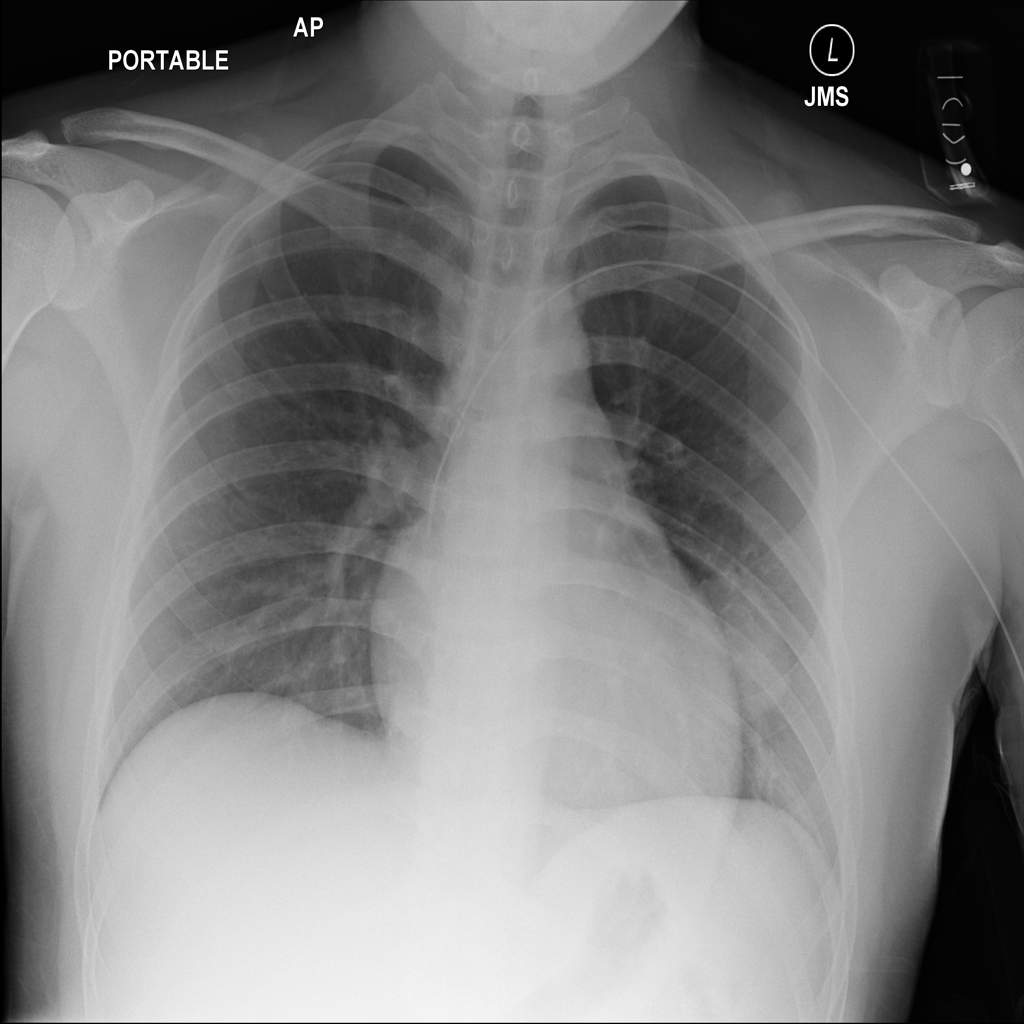

PAT-4639 · IMG-024Mass

PAT-4639 · IMG-024

AP